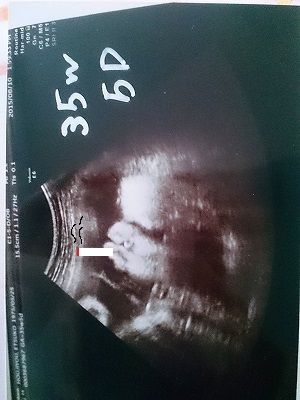

不妊治療を経て、検診の時。

げっっっ・・・。下唇めっちゃ飛び出とるし、まるでタバコでもくわえて一服してるかのような・・・。だめだこりゃ~って顔やんっ(笑)よしっ。オマエはほんこんか千原せいじの路線で楽しく頑張れ!とおちゃんはどっちも大好きやから大丈夫や!!って、ホンマに思ったな~

2015年1月2日不妊治療で通ったクリニックに治療結果を聞きに行ってキミがママのお腹におることを知りました。あちこち病院を変えては不妊治療を続け、気がつけば3年ママもよく頑張ってくれました神戸元町夢クリニック。お世話になりました!いや~。長かった!さー!はよ